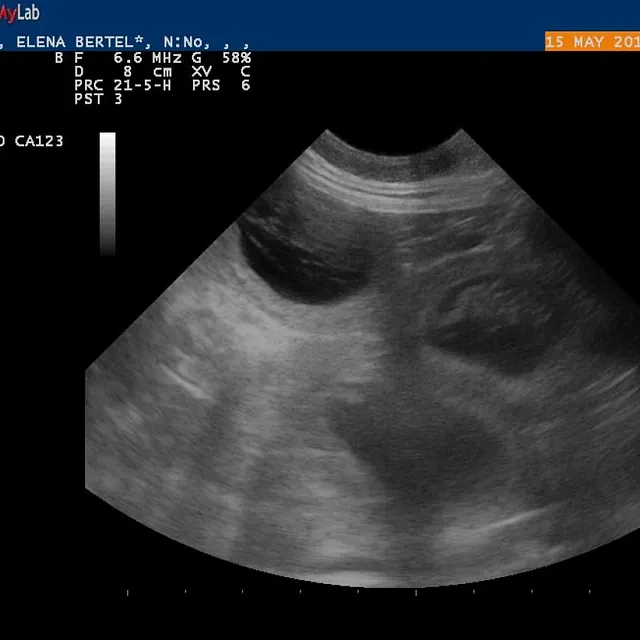

15.05.2017

Alice er drægtig!

e-kuld, 2017, sommer, kennel basta dog, schnauzere, schnauzerhvalpe, schnauzeropdræt, mellemschnauzer, alenzo, alice, hvalpe, købe schnauzer

Dejlig, dejlig nyhed!!!

Alice (Allegra)  er drægtig!

Scanning i dag har nemlig bekræftet den dejlige nyhed!

Hvor mange hvalpe er der inde? Tja, en del af dem kan du se på de billeder fra scanning :)

Nu krydser vi fingre for at alt går godt og vi får dejlige hvalpe efter de smukke og dygtige forældre!

P.S. Scaninngsbillederne ved klik på dem vil kunne ses i større størelse!